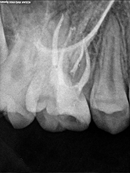

Root Canal Cases